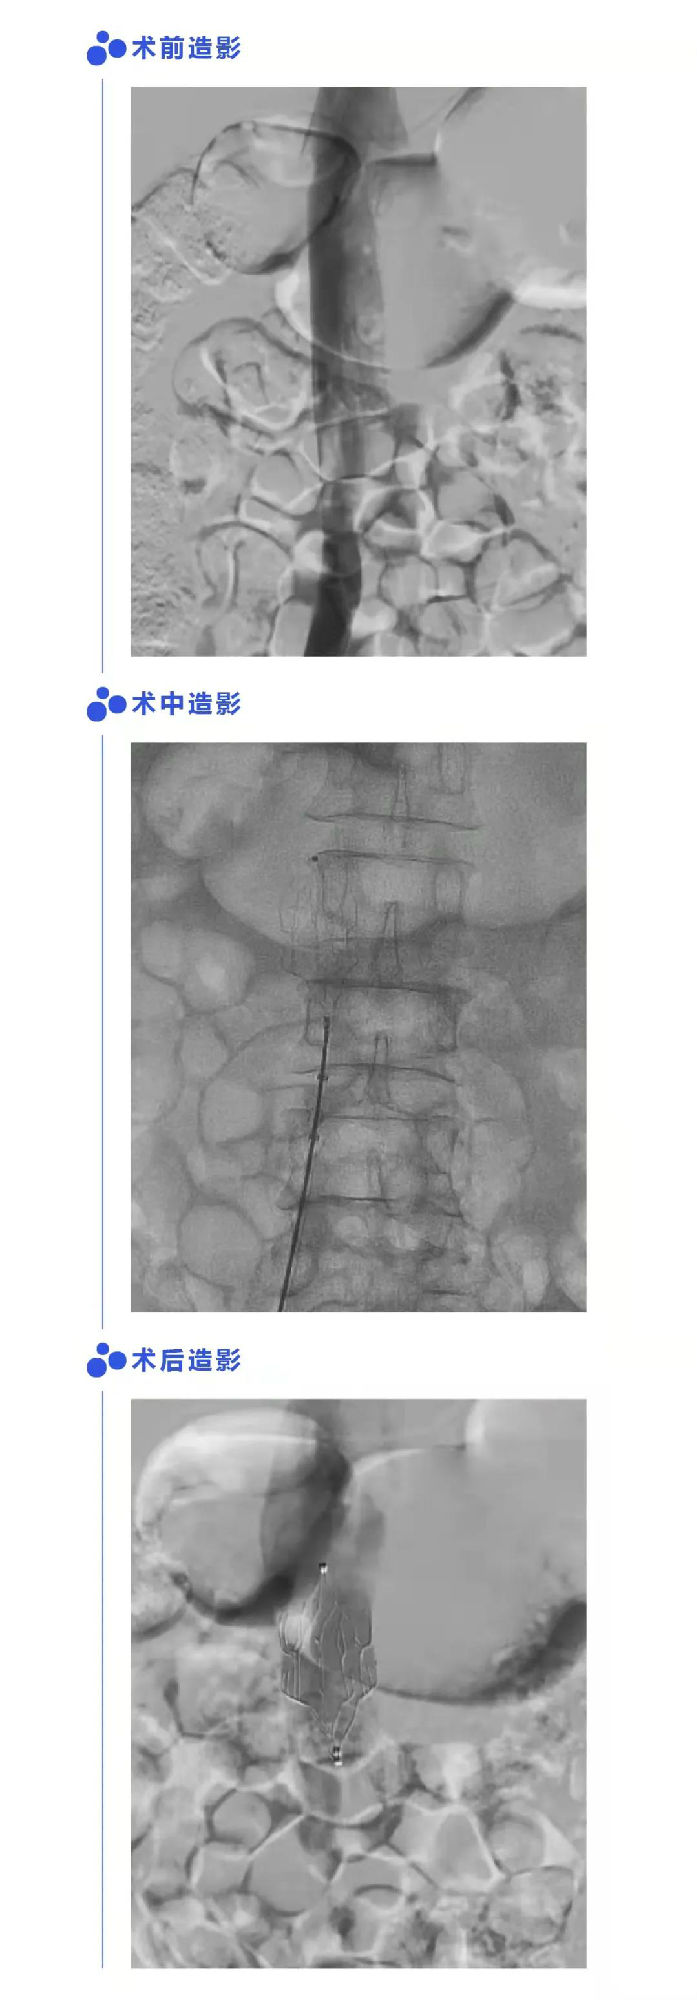

患者男,57岁,因表伤至左髌骨骨折,术前超声提醒左侧腘静脉有血栓形成。经评估切合手术指征,植入Fitaya?腔静脉滤器,滤器定位正确,状态好;经血栓断根和抗凝医治后血栓隐没,置入术后56天顺利取出滤器,无移位、倾斜。取出术后24天随访,超声提醒下腔静脉畅达,原滤器置入部位无血栓形成。